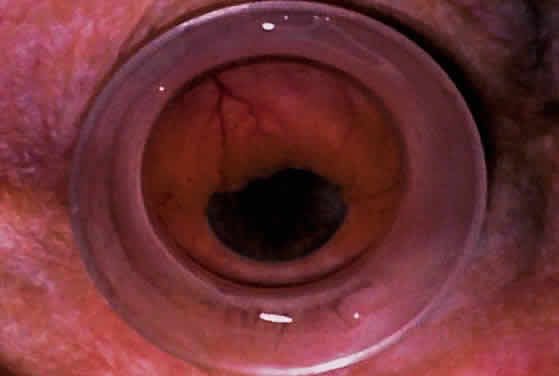

CATARACT AND INTRAOCULAR LENS The role of UBM in the preoperative assessment of eyes with cataract is

as yet unknown. In certain eyes, however, UBM may reveal features or

abnormalities that could alter the ophthalmologist's surgical approach. Postoperatively, UBM can show the size and location of an intraocular

lens (IOL) and the positioning of the haptics. A posterior chamber

IOL appears on UBM as a highly reflective plate (corresponding to

the lens optic) in the retropupillary plane with reverberation artifacts

behind it (Fig. 17A). In contrast, an anterior chamber IOL appears on UBM as a sonoreflective

plate located anterior to the pupillary plane (see Fig. 17B). In most eyes with a posterior chamber IOL, UBM can show whether the

haptics are in the capsular bag (Fig. 18A), in the ciliary sulcus (see Fig. 18B), or in some other anatomic location12 (e.g., resting on the peripheral iris or secured with sutures to the sclera). The

haptics are easier to locate if they are made of polymethyl-methacrylate

than if they are made of proline because the former has a stronger

reflectance.  Fig. 17. Composite UBM images of intraocular lenses. A. Posterior chamber IOL. B. Anterior chamber IOL. Fig. 17. Composite UBM images of intraocular lenses. A. Posterior chamber IOL. B. Anterior chamber IOL.

|

Fig. 18 . Localization of posterior chamber IOL haptics by UBM. A. Haptic in capsular bag (arrow). B. Haptic (bright object just behind peripheral iris) in iridociliary sulcus. Fig. 18 . Localization of posterior chamber IOL haptics by UBM. A. Haptic in capsular bag (arrow). B. Haptic (bright object just behind peripheral iris) in iridociliary sulcus.